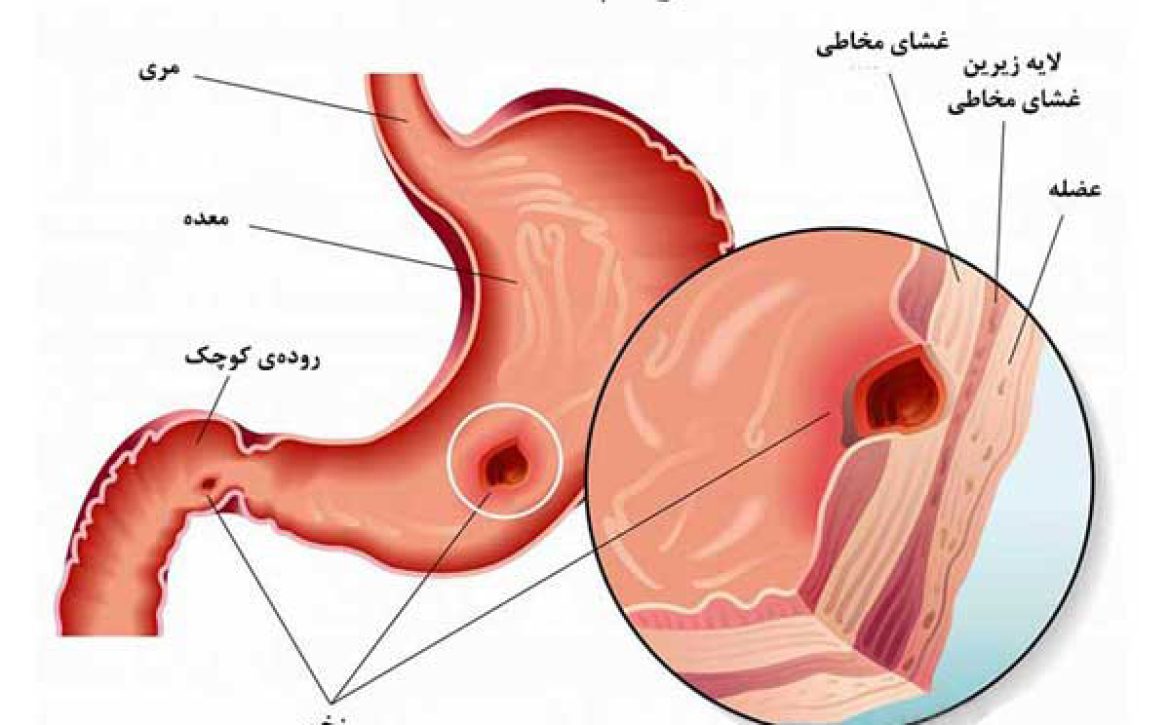

زخم معده چیست؟

زخم معده یا زخم پپتیک به آسیب و ایجاد زخم در لایهی داخلی معده یا بخش ابتدایی رودهی کوچک (اثنیعشر) گفته میشود. بهطور طبیعی، مخاط ضخیمی از معده در برابر اثرات مخرب اسید معده محافظت میکند؛ اما در برخی شرایط، این لایه محافظ آسیب دیده و زمینه برای ایجاد زخم فراهم میشود.زخم معده یا زخم پپتیک به آسیب و ایجاد زخم در لایهی داخلی معده یا بخش ابتدایی رودهی کوچک (اثنیعشر) گفته میشود. بهطور طبیعی، مخاط ضخیمی از معده در برابر اثرات مخرب اسید معده محافظت میکند؛ اما در برخی شرایط، این لایه محافظ آسیب دیده و زمینه برای ایجاد زخم فراهم میشود.

در واقع آسیب به لایه محافظ معده، باعث تماس مستقیم اسید با بافت داخلی و در نهایت ایجاد زخم میشود.